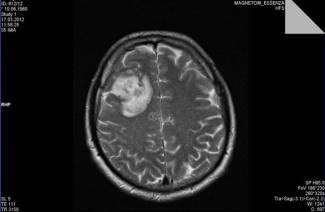

Subarachnoidálne krvácanie z choroby má svoju vlastnú klasifikáciu. Stanovuje sa pomocou základných údajov získaných z CT alebo MRI. Výpočty zahŕňajú masívne krvácanie, kombináciu s parenchymálnym, komorovým krvácaním v lebečnej dutine. Podľa výsledkov diagnózy sa určuje, čo je subarachnoidálne krvácanie: izolované, parenchymálne, komorové alebo parenchymálne-komorové krvácanie.

Potom vykonajte krvný test, aby ste určili zrážanlivosť krvi. Potom sa uskutoční lumbálna punkcia. Za týmto účelom zoberte špeciálnu ihlu a vpichnite do bedrovej oblasti niekoľko milimetrov a extrahujte niekoľko mililitrov mozgovej miechy. Ak je v mozgovomiechovom moku malé množstvo krvi (zrazenín), v subarachnoidálnom priestore sa vyskytlo krvácanie. Na štúdium štruktúry mozgu a zistenie miesta krvácania sa vykonáva počítačová a magnetická rezonancia.

Echoencefalografia môže určiť intrakraniálne subarachnoidálne krvácanie, ktoré môže vytlačiť mozog. Pomocou transkraniálnej dopplerografie môžete vyhodnotiť prietok krvi v mozgových tepnách. Pomôže to zistiť, kde dochádza k vazokonstrikcii. Pomocou angiografie magnetickou rezonanciou môžete vyhodnotiť integritu mozgových tepien, ich vodivosť.

Primárna hospitalizácia pacientov s SAH sa vykonáva v primárnych alebo regionálnych vaskulárnych centrách. Na lôžkových oddeleniach sa pacient podrobuje všetkým procedúram, ktoré pomôžu diagnostikovať ochorenie - MRI mozgu na určenie subarachnoidálneho krvácania (existuje intenzívna biela oblasť) a neinvazívne vyšetrenie cievneho systému (MRI angiografia). Ak sa počas týchto zákrokov zistila neprítomnosť príznakov, je predpísaná bedrová punkcia.